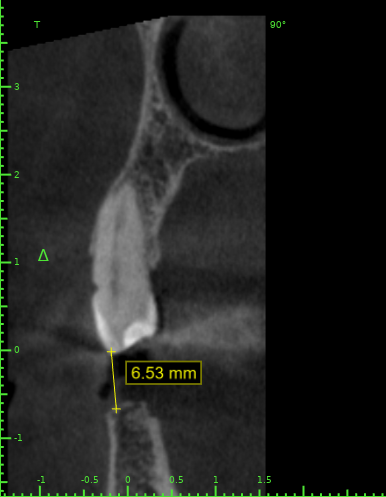

Женька Опубликовано 10 декабря, 2021 Поделиться Опубликовано 10 декабря, 2021 Клинически показалось очень мало места для адекватной коронки. Не помешает ли вестибулярная кортика интрузии? Ссылка на комментарий

АнтонТЛТ Опубликовано 10 декабря, 2021 Поделиться Опубликовано 10 декабря, 2021 А ортопед не хочет немного шлифануть этот зуб? Винты ставить из-за 1.5 мм, как-то жёстко) Планирование в каком софте? 2 Ссылка на комментарий

Bier Опубликовано 12 декабря, 2021 Поделиться Опубликовано 12 декабря, 2021 поднять зуб менее инвазивно, чем его пилить. Ссылка на комментарий

annda Опубликовано 17 декабря, 2021 Поделиться Опубликовано 17 декабря, 2021 (изменено) Тут весь прикус поднимать надо, с заменой протетики слева и восстановлением стертых резцов и клыков , а вы про инвазию на премоляре:)) Изменено 17 декабря, 2021 пользователем annda 1 Ссылка на комментарий